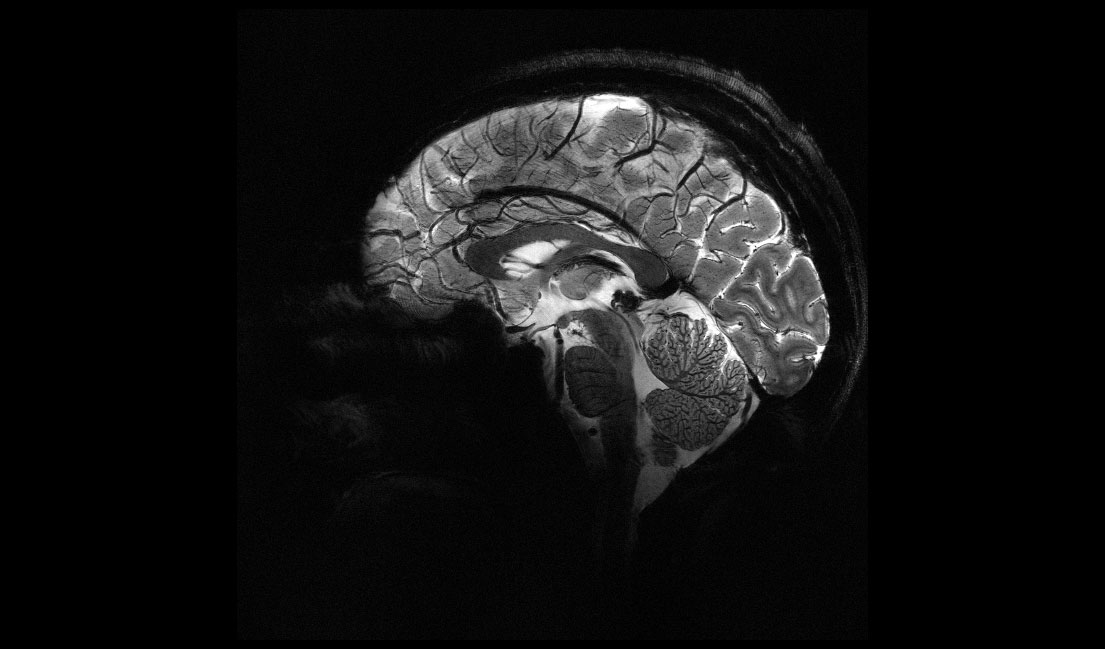

Zobrazovacou metódou MRI sa v súčasnosti už bežne skúmajú tkanivá a orgány v ľudskom tele, pričom získané podrobné snímky pomáhajú presnejšie diagnostikovať najmä rôzne druhy nádorových ochorení. NMR spektroskopia nachádza široké uplatnenie aj v materiálovej chémii, farmaceutickom priemysle a vo fyzike pevných látok. Na získanie čo najlepšej rozlišovacej schopnosti a zobrazení aj tých najmenších detailov skúmanej štruktúry musí NMR spektroskop disponovať magnetom, vytvárajúcim čo najsilnejšie magnetické pole (najvyššiu magnetickú indukciu). Konvenčné MRI prístroje používané v nemocniciach na diagnostiku pracujú s magnetmi produkujúcimi magnetické pole s intenzitou 1,5 až 3 T, pričom T je jednotka magnetického toku (indukcie), ktorej dal meno srbsko-americký inžinier Nikola Tesla.

Francúzska Komisia pre atómovú energiu a alternatívne energie nedávno oznámila, že vyvinula MRI spektroskop pracujúci s magnetom produkujúcim rekordné pole 11,7 T. Ide o supravodivý magnet chladený kvapalným héliom na teplotu −271,35 °C. Zásobník hélia má objem 7 500 litrov. Magnet je navinutý zo supravodivého vodiča celkovej dĺžky 182 km.

Kompletné zariadenie na MRI zobrazovanie má hmotnosť 132 ton, dĺžku 5 m a šírku 5 m. Otvor pre pacientov má priemer až 90 cm, teda podstatne viac než obvyklých 60 až 70 cm, čo je veľkou výhodou pre ľudí trpiacich klaustrofóbiou.